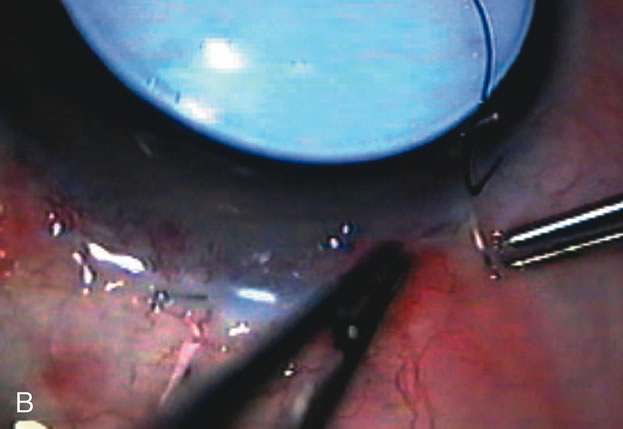

Fig. 4. Viscocanalostomy with deep sclerectomy and phacoemulsification. Nonpenetrating filtration procedures (NPFS) may be combined with phacoemulsification. Patients with mild disc damage and a history of limited topical drug therapy are the best candidates. Patients who require an IOP in the low teens are not good candidates for NPFS. By definition, NPFS is designed to lower IOP without penetrating into the anterior chamber, thereby avoiding the complications associated with trabeculectomy. Viscocanalostomy is intended to allow aqueous to percolate through a trabeculodescemetic membrane into a subscleral cavern created by the deep sclerectomy. The aqueous diffuses from the cavern into the dilated ostia of Schlemm's canal and into the episcleral venous plexus. A. Fashion a uniform 300-micron superficial scleral flap 1 mm into clear cornea. B. Construct a second 600-micron deep flap that facilitates the unroofing of Schlemm's canal, seen as the darker area. C. Use viscoelastic to dilate the ostia of Schlemm's canal. The major problem with viscocanalostomy is the eventual closure of the ostium decreasing flow to the episcleral plexus. D. Dissect the deep flap anteriorly into clear cornea creating the trabeculodescemetic membrane. This membrane is clearly seen between the scleral spur and the bend of the deep flap. The integrity of this membrane ensures the nonpenetrating portion of the surgery. Another problem with NPFS is the eventual fibrosis of this initially transparent membrane requiring goniopuncture. E. Deep sclerectomy gets its name from removal of the deep flap. Removal of this flap creates the potential subscleral space for accumulation of aqueous before it enters Schlemm's canal and exits the episcleral venous plexus. After removal of the deep flap, the superficial flap is sutured into place and conjunctiva closed. Approximately half of these procedures develop a shallow bleb.